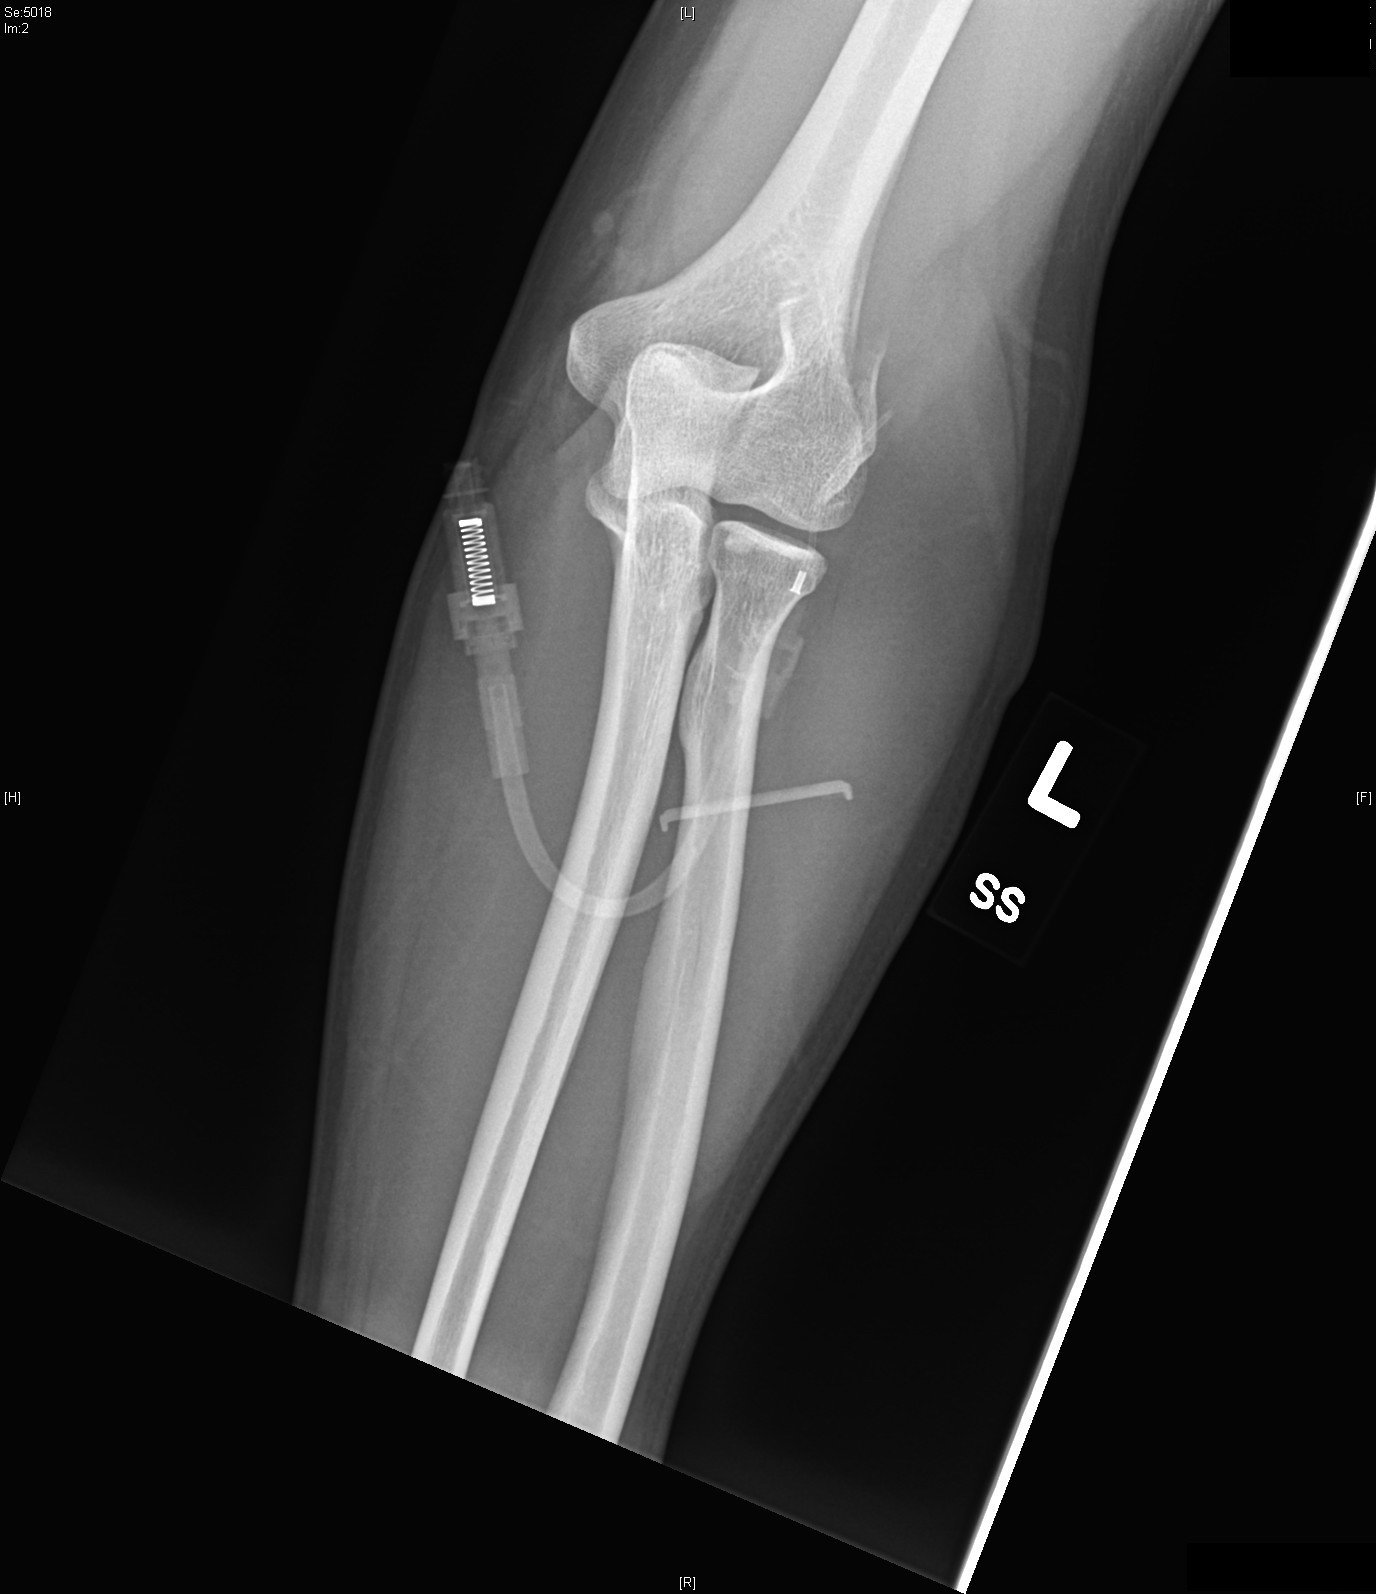

Radiographs of the right elbow revealed an acute fracture through the lateral epicondyle with dislocation of the radial head inferiorly. Radiographs of the left elbow revealed a slightly angulated fracture through the lateral epicondyle.

Given the patient’s bilateral condylar fractures, orthopedics was consulted and recommended reduction of the dislocated right radial head with bilateral splinting. Post-reduction films revealed successful reduction and patient was neurovascularly intact before and after the procedure. The patient was discharged with instructions for short interval follow up in the orthopedics clinic to discuss the necessity for surgical management of the fractures.